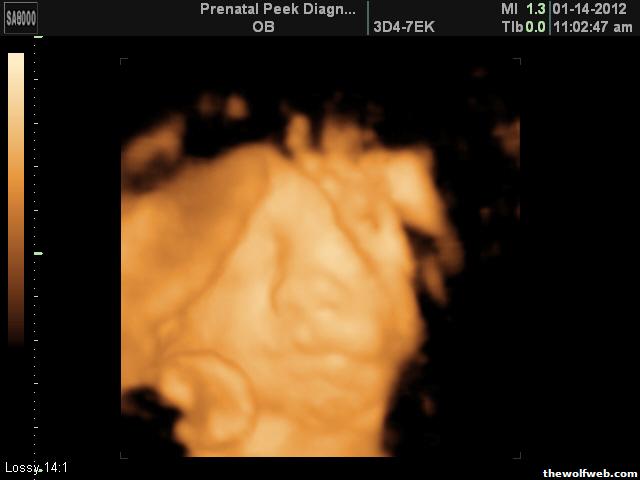

Photo Gallery » scotieb24 » Family » Baby Brame

Baby Brame